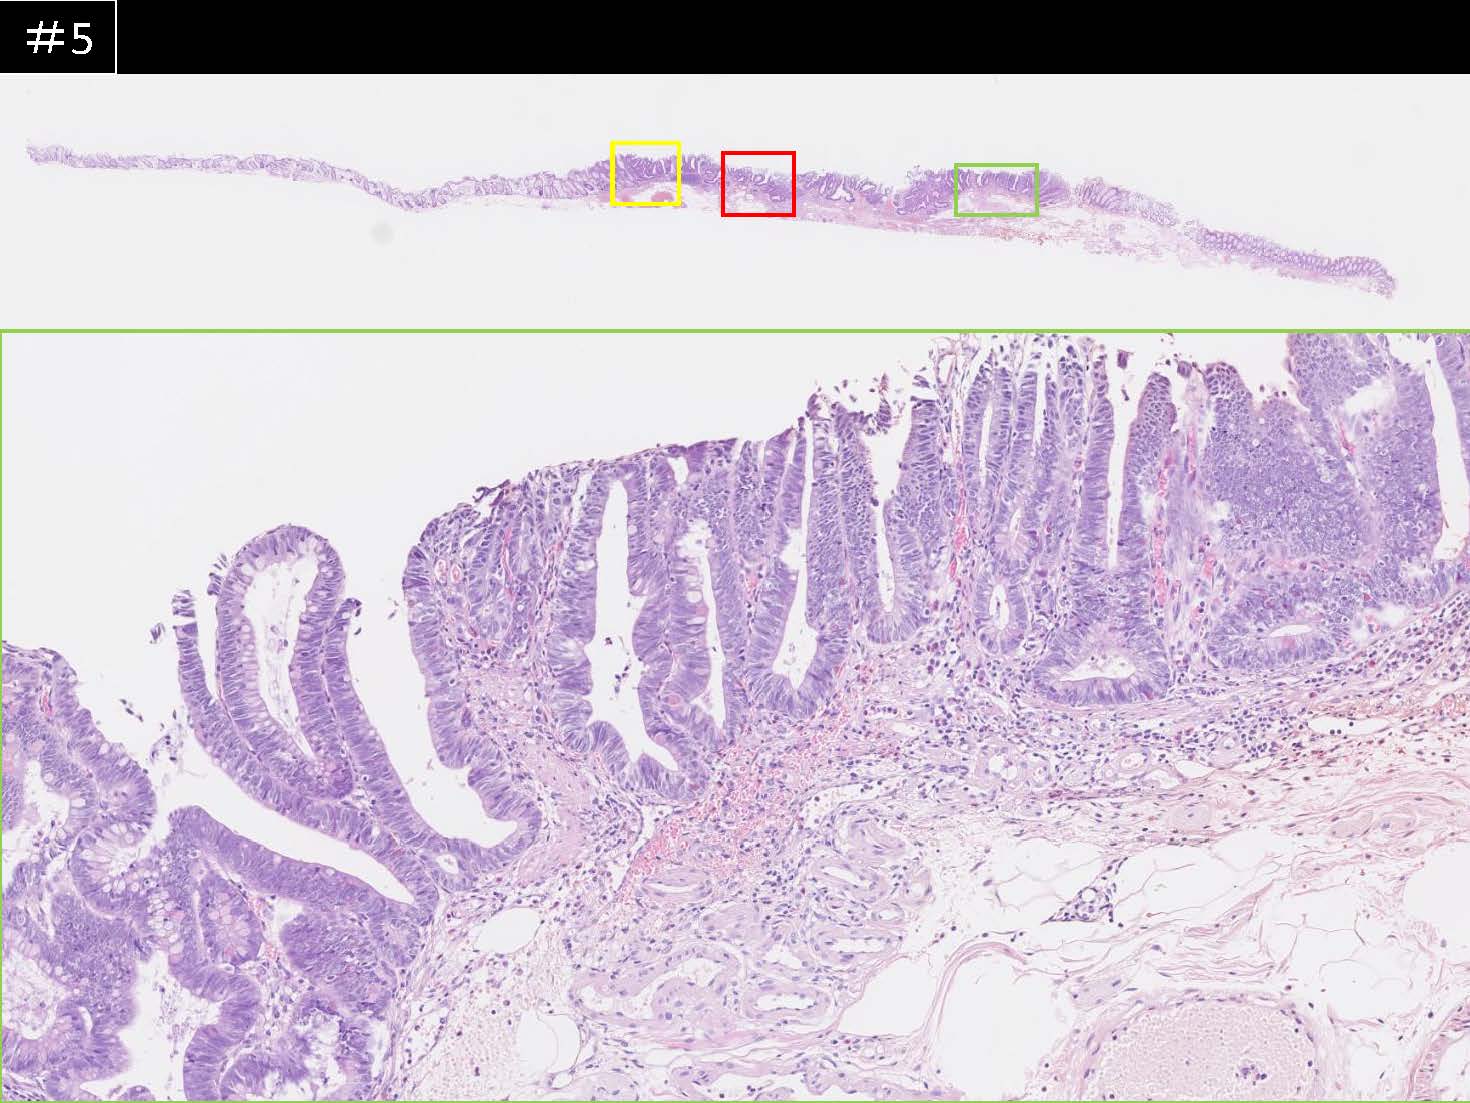

消化管Mapping~大腸~ 2021.10.27

消化管Mapping~大腸~

消化管Mapping

全ページPDFのダウンロードはこちら